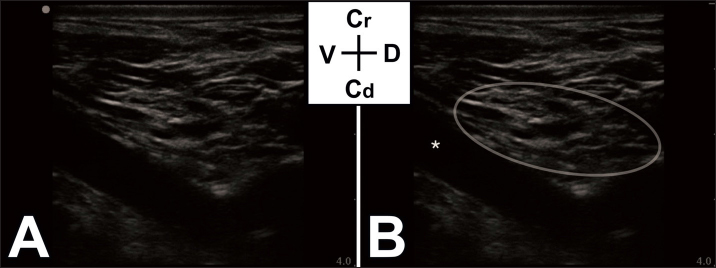

In lateral recumbency, after trichotomy and surgical scrub of the area, the brachial plexus was localized at the level of the right axilla using a 13-6 MHz linear ultrasound transducer (SonoSite Edge, FUJIFILM Sonosite, Netherlands) (Fig. 1), and a total volume of 16 ml of ropivacaine 0.75% (2 mg/kg, Naropine, AstraZeneca, UK) was injected perineurally under ultrasound-guidance (Fig. 2).

Fig. 2. (A): Ultrasound image of the brachial plexus, obtained at the level of the chosen acoustic window. (B): Same image with added landmarks. Ellipse – target area of the brachial plexus. Asterisk – carotid artery.